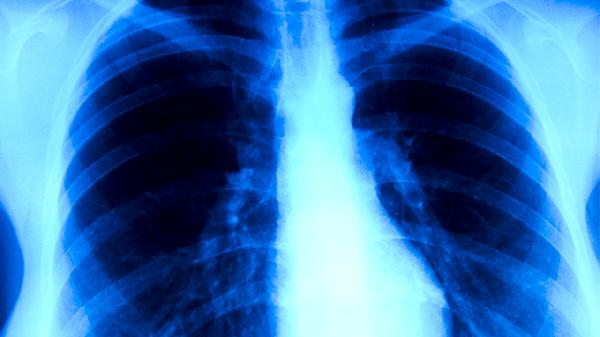

肺结核患者需严格遵循早期、联合、适量、规律、全程的用药原则,完成6-9个月的标准疗程。治疗期间应保持高蛋白饮食,适当补充维生素和微量元素,避免饮酒和过度劳累。定期复查胸部影像学和痰菌检查,观察药物疗效及不良反应。出现皮疹、黄疸、视力模糊等异常症状应及时就医,不可自行调整用药方案。居住环境需保持通风干燥,密切接触者应进行结核筛查。